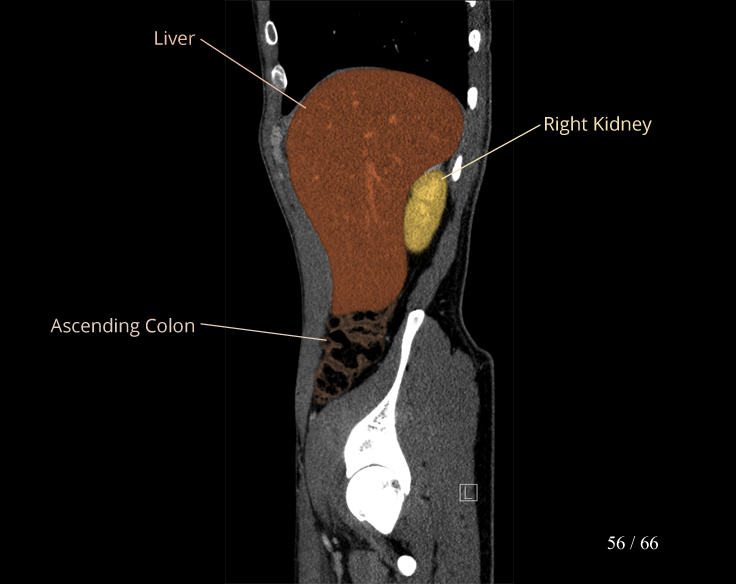

Body

Covers abdominal CT anatomy.